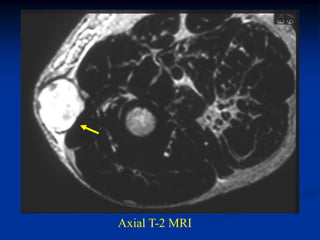

Case #264.1

78 year old female with painful mass forearm for 4 months

Sag T-1   T-2   Gad

Axial T-1         T-2

Gad

Case #264.1 78 year old female with painful mass forearm for 4 months

Axial T-1 T-2 Gad